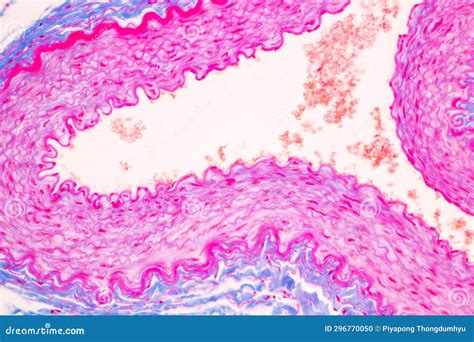

Once the tissue is prepared, it can be observed under a light microscope. Key features to look for include:

• Neurons: Identify the cell bodies (soma), dendrites, and axons. Neurons have a characteristic star-shaped appearance due to their numerous processes.

• Neuroglia: Look for glial cells, which are smaller and more numerous than neurons. They provide structural support and insulation for neurons.

• Myelin Sheaths: Observe the white, fatty substance that wraps around axons, providing insulation and increasing the speed of signal transmission.

• Nerve Fibers: These are bundles of axons that transmit signals over long distances. They are often seen in cross-section as circular structures.

🔍 Note: When observing nervous tissue, it is essential to use appropriate magnification. Lower magnification (e.g., 10x or 20x) provides an overview of the tissue structure, while higher magnification (e.g., 40x or 100x) allows for detailed examination of individual cells and their components.